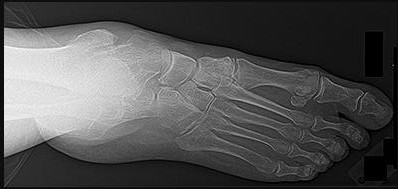

Question 37:

A 24-year-old football player sustains a high-energy hyperplantarflexion midfoot injury. Weight-bearing radiographs show a 2.5 mm widening between the base of the first and second metatarsals. An avulsion fracture ('Fleck sign') is seen. The structure avulsed normally attaches to which two bones?

Options:

- Medial cuneiform and base of the first metatarsal

- Middle cuneiform and base of the second metatarsal

- Medial cuneiform and base of the second metatarsal

- Lateral cuneiform and cuboid

- Navicular and medial cuneiform

Correct Answer: Medial cuneiform and base of the second metatarsal

Explanation:

The 'Fleck sign' represents an avulsion of the Lisfranc ligament. This critical, stout ligament originates on the lateral aspect of the medial cuneiform and inserts on the medial aspect of the base of the second metatarsal. It is the primary stabilizer of the midfoot, as there is no direct ligamentous connection between the first and second metatarsal bases.